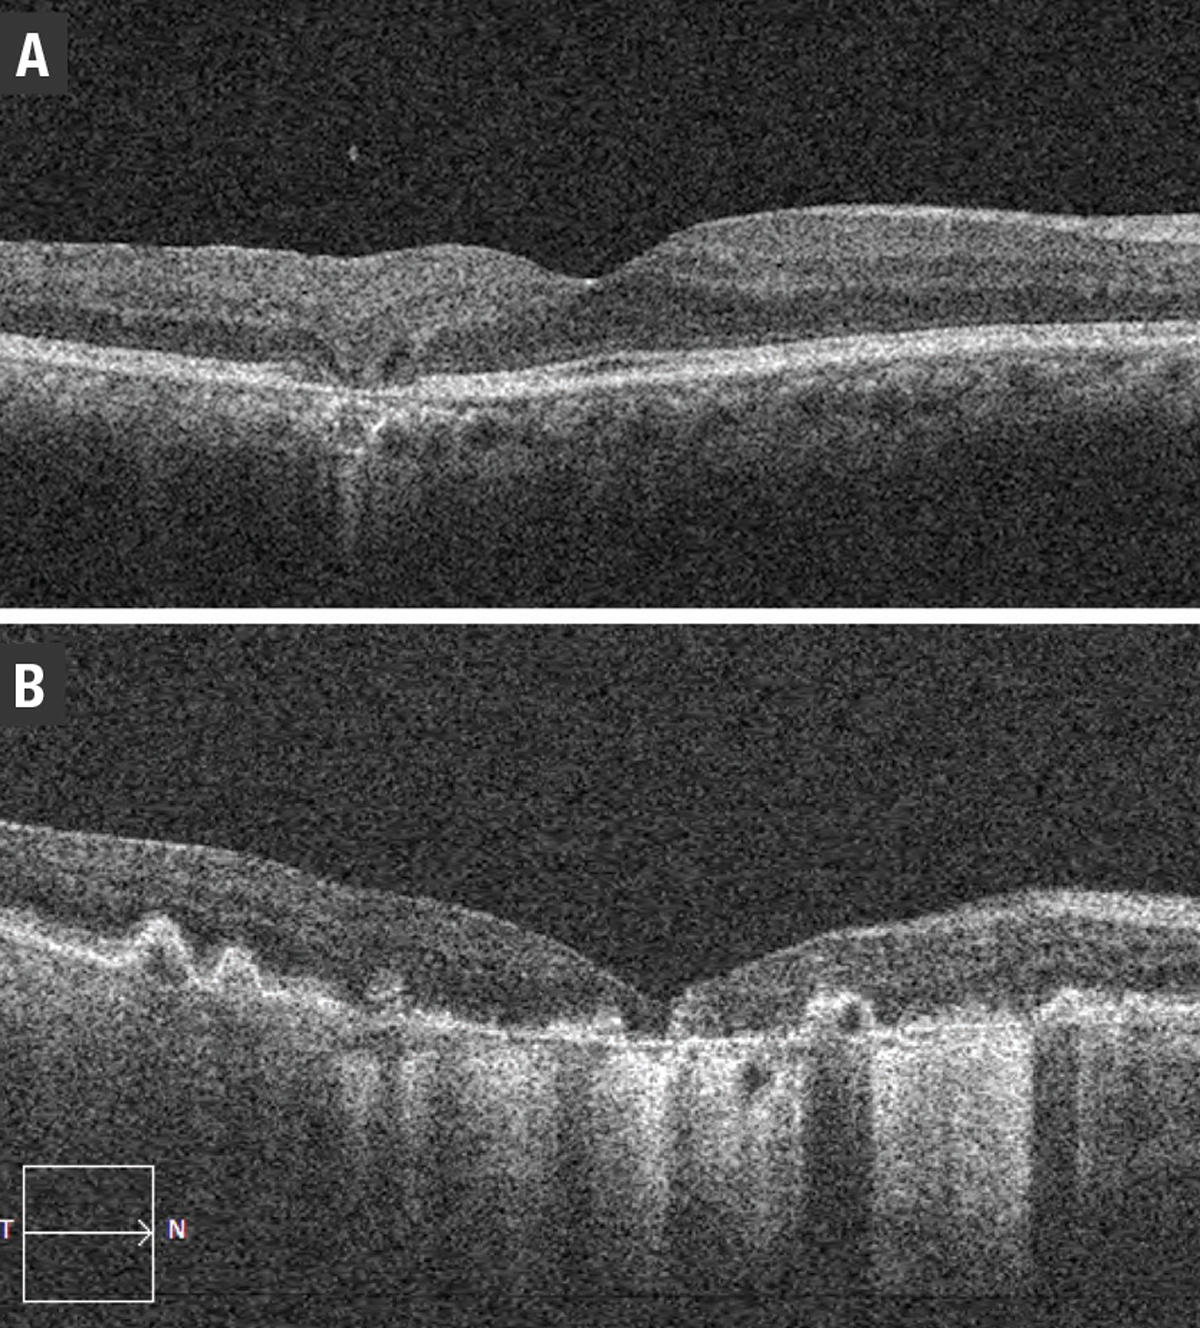

![]() |

| Figure 9. Optical coherence tomography shows: A) degenerative intraretinal cystoid lesions overlying a disciform scar; and B) outer retinal tubulation. |